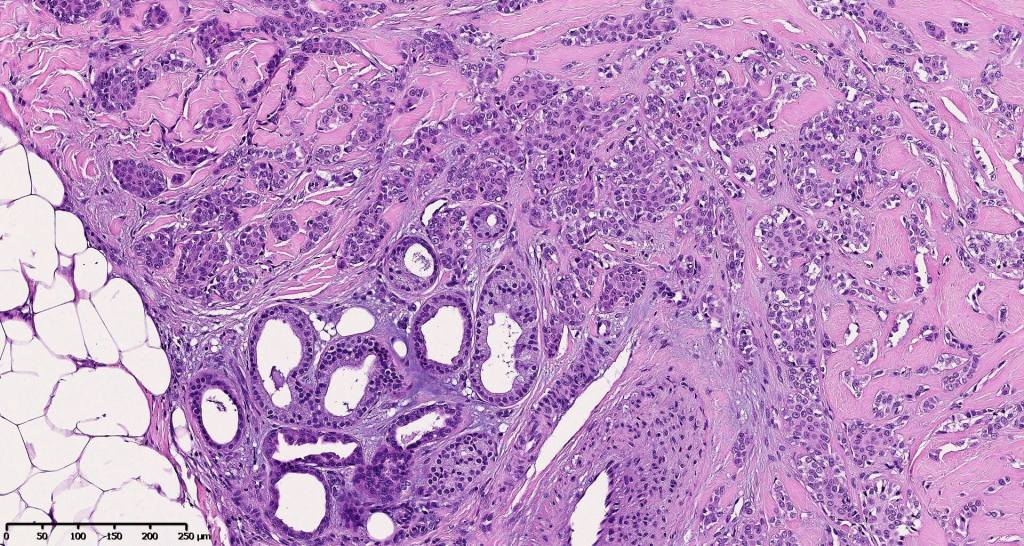

•Well circumscribed unencapsulated, nodular/multinodular silhouette composed of an admixture of epithelial & mesenchymal elements

•Mixed epithelial component including nests & cords of epithelium with abundant, eosinophilic cytoplasm & small vesicular nuclei

•Glandular differentiation sometimes showing apocrine differentiation

•Myoepithelial layer in glandular foci

•Ductal differentiation

•Plasmacytoid myoepithelial cells; clear cell change

•Myxoid change

•So-called eccrine variant characterized by a pure population of small ducts compressed by dense collagen